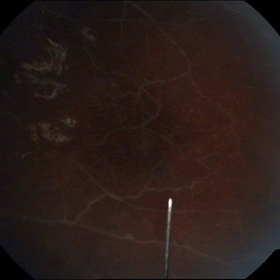

Proliferative Diabetic Retinopathy

Sep 20 2014 by Mehul A Shah

A 55-year-old diabetic presented with sudden loss of vision and on examination he had pdr with tractional deachment.

Photographer: Drashti Netralaya,Dahod

Imaging device: Zeiss ff450

Condition/keywords: proliferative diabetic retinopathy (PDR)